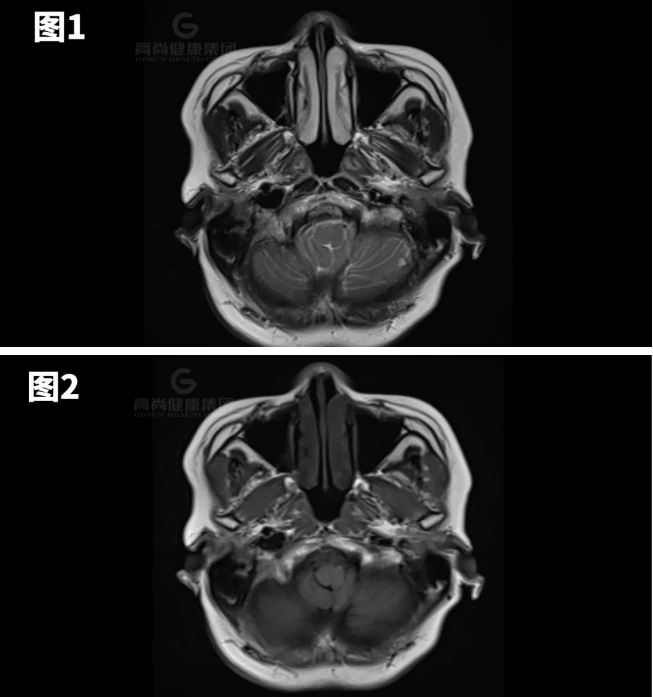

图1-7示小脑扁桃体向下疝出约8mm。

矢状位:扁桃体延伸到枕骨大孔下方,脑干压迫斜坡。

横断位:移位的扁桃体导致周围脑脊液闭塞、髓质前移以及脊髓动脉和椎动脉受压。